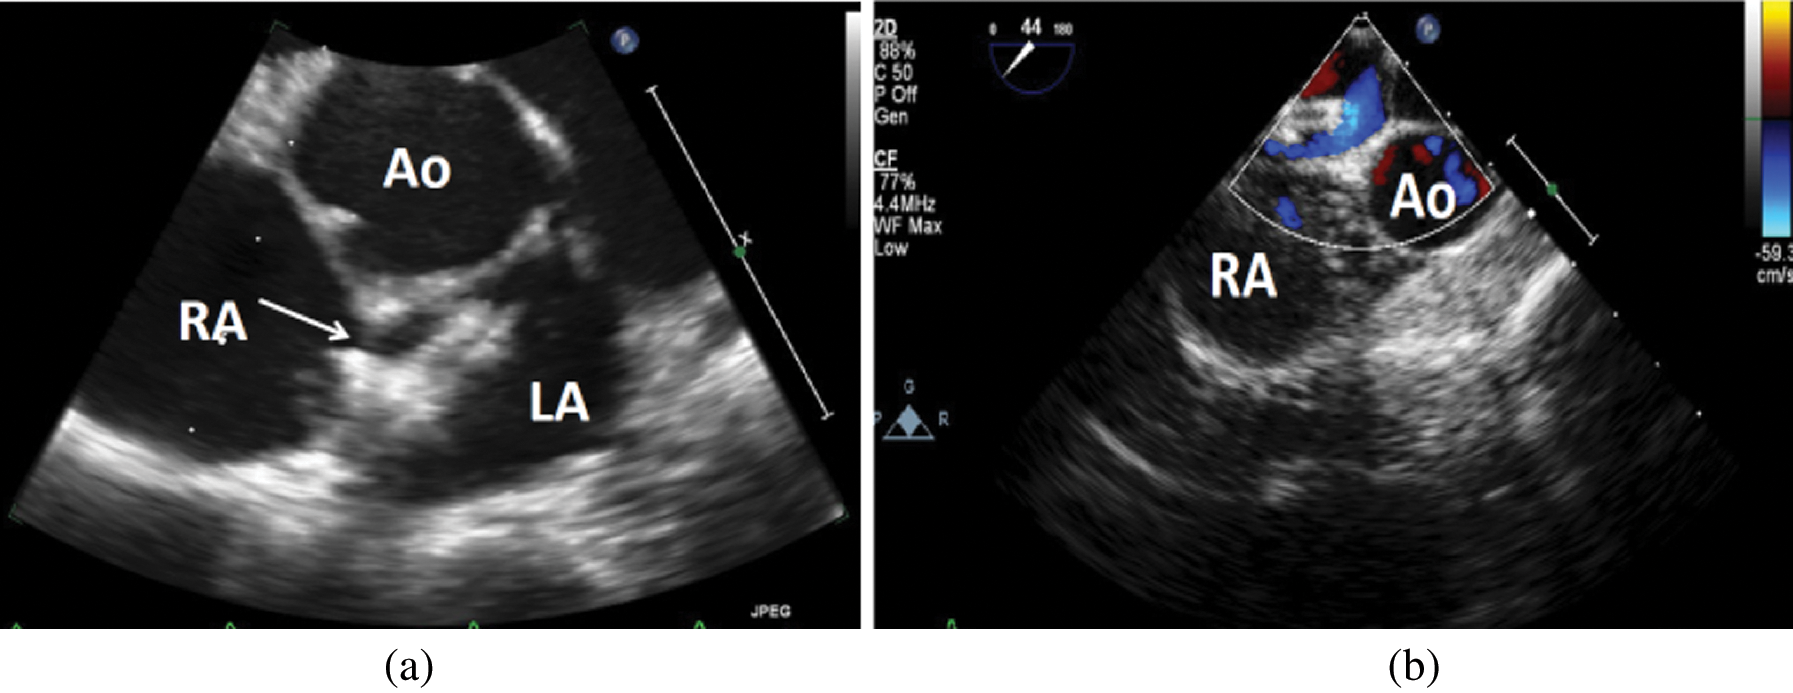

Management of Atrial septal defect Device closure lagging behind Asd Closure Device Failure Primum, sinus venosus, and coronary sinus asds. Although most asds are amenable to device closure, limitations exist related to absolute size of the defect; Size of the defect in relationship. Summary of the key features of transcatheter closure of asds and vsds, including types of defects amenable to device closure, and devices. Closure of large atrial septal defects using the. Asd Closure Device Failure.